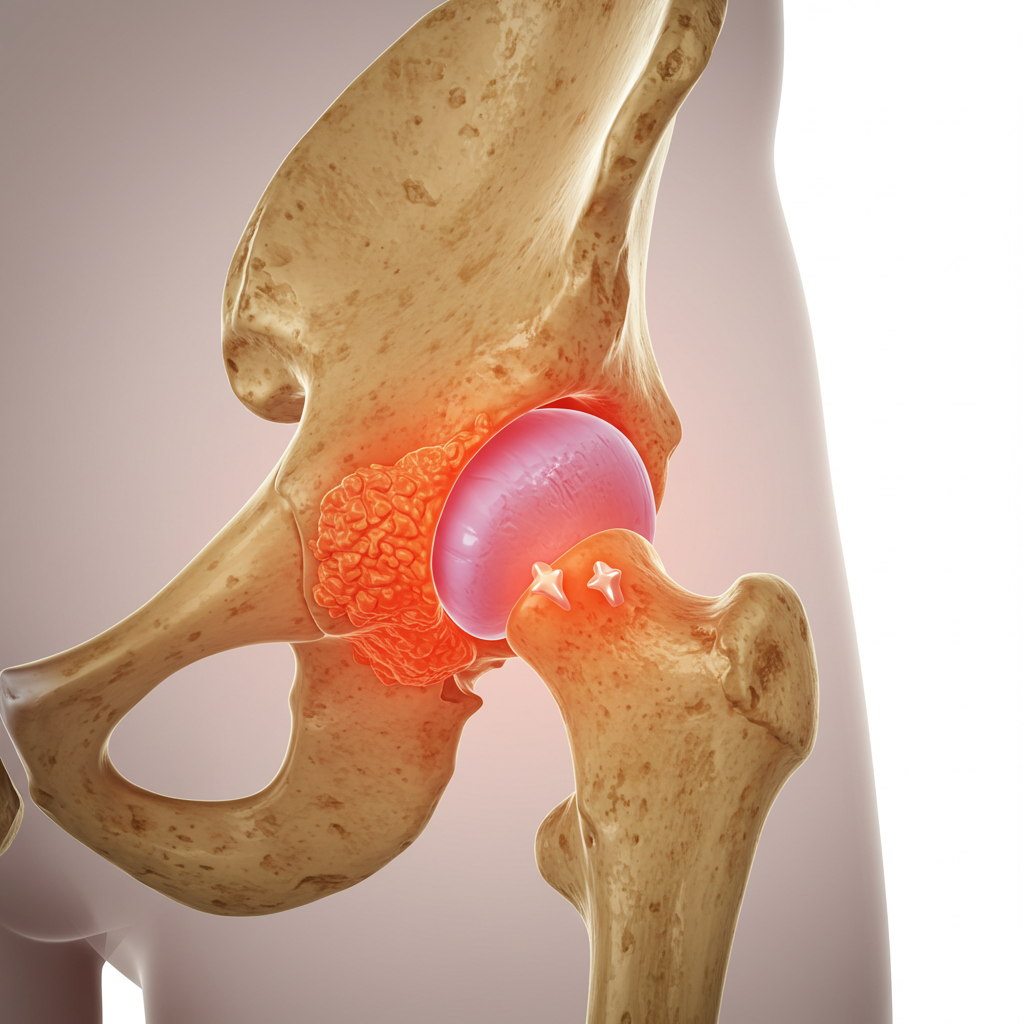

Sinovitis de Cadera

¿Qué es?

Inflamación de la membrana sinovial que recubre la articulación, común en niños pero también presente en adultos.

Síntomas:

- Dolor agudo en la cadera

- Cojera repentina

- Limitación de movimiento -

Tratamiento:

- Reposo y control del dolor

- Antiinflamatorios

- Seguimiento clínico con estudios de imagen